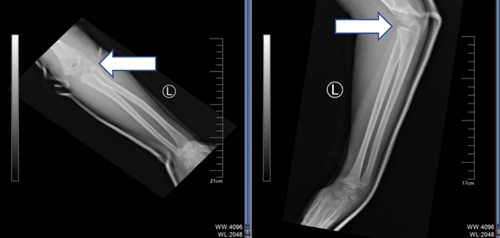

02 病例二

另有一名 8 歲男孩,在家中玩耍時(shí)不慎從椅子上摔落,左胳膊當(dāng)場(chǎng)彎成畸形,被家長(zhǎng)緊急帶至青島市婦女兒童醫(yī)院兒童骨折整復(fù)門診。經(jīng)拍片檢查確認(rèn)是左肘關(guān)節(jié)脫位合并左尺骨近端、左肱骨遠(yuǎn)端多處骨折。隨后,該門診醫(yī)生為患兒進(jìn)行了手法整復(fù),孩子受傷的胳膊恢復(fù)原貌,拍片顯示骨折處已經(jīng)復(fù)位成功,家長(zhǎng)連連道謝。

復(fù)位前

復(fù)位后